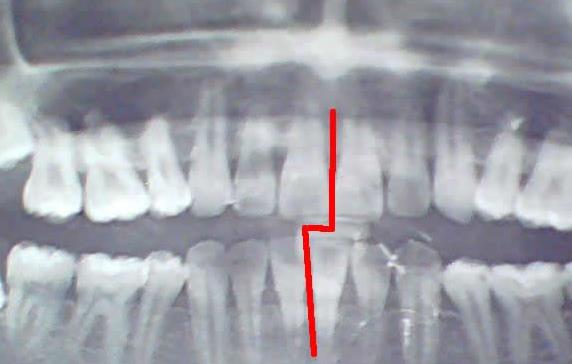

矯正後中線不齊

深圳牙科醫院醫生介紹,牙齒矯正成功的標準是:牙齒排列整齊,牙齒咬合關(guan) 係正常、符合牙齒美觀的中線對齊等常見的標準,牙齒矯正是需要一兩(liang) 年的過程,所以需要堅持下來,這是重要的。不少人雄心勃勃的開始矯正,但是在中途放棄了,而且不能接著矯正,隻能重新再來了,這種是典型的沒有毅力造成的。